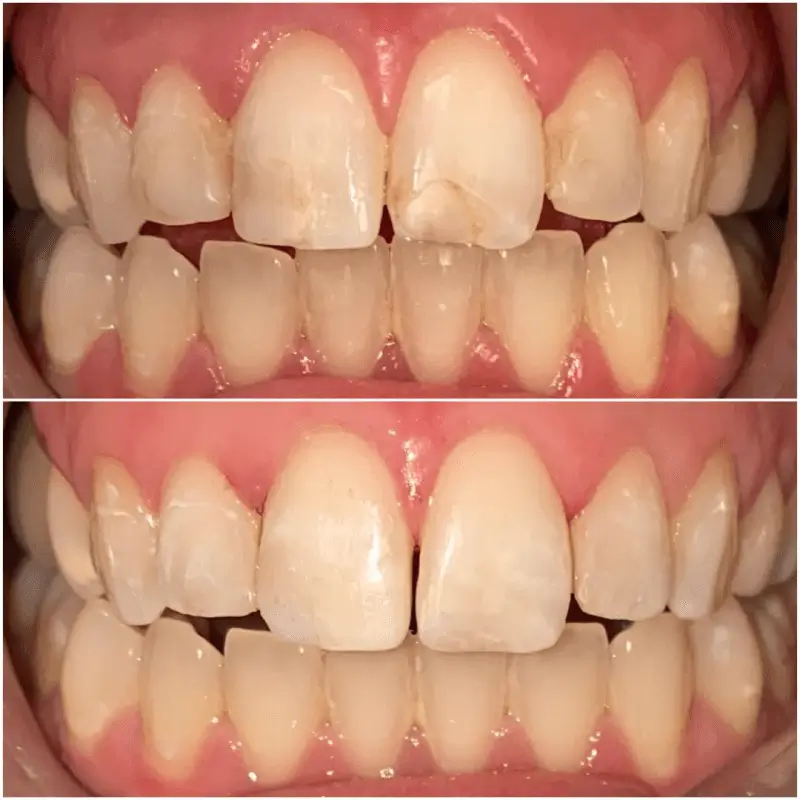

Patient presented to the office with a concern about spaces between the teeth and slight discoloration.

A detailed smile analysis with initial pictures, x rays, a scan of the teeth was used to fabricate a mock up smile.

Patient presented to the office unhappy with the old composite restorations but did not want anything extensive. Patients goal was to re do the composite bondings.

Patient presented to the office with the complaint of stained older restorations, minor crowding and alignment issues that had started to bother her. She did not want to undergo invisalign or traditional braces.